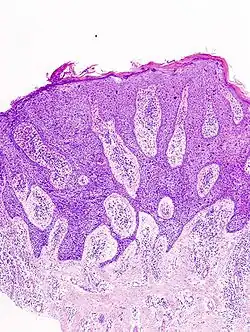

Histological characteristics

Histopathologically, the epidermis in cSCC in situ (Bowen's disease) will show hyperkeratosis and parakeratosis. There will also be marked acanthosis with elongation and thickening of the rete ridges. These changes will overly keratinocytic cells, which are often highly atypical and may have a more unusual appearance than invasive cSCC. The atypia spans the full thickness of the epidermis, with the keratinocytes demonstrating intense mitotic activity, pleomorphism, and greatly enlarged nuclei. They will also show a loss of maturity and polarity, giving the epidermis a disordered or "windblown" appearance.

Two types of multinucleated cells may be seen: the first will present as a multinucleated giant cell, and the second will appear as a dyskeratotic cell engulfed in the cytoplasm of a keratinocyte. Occasionally, cells of the upper epidermis will undergo vacuolization, demonstrating an abundant and strongly eosinophilic cytoplasm. There may be a mild to moderate lymphohistiocytic infiltrate detected in the upper dermis.[12]

In situ disease

Bowen's disease is essentially equivalent to and used interchangeably with cSCC in situ, when not having invaded through the basement membrane.[12] Depending on source, it is classified as precancerous[13] or cSCC in situ (technically cancerous but non-invasive).[48][49] In cSCC in situ (Bowen's disease), atypical squamous cells proliferate through the whole thickness of the epidermis.[12] The entire tumor is confined to the epidermis and does not invade into the dermis.[12] The cells are often highly atypical under the microscope, and may look more unusual than the cells of some invasive squamous-cell carcinomas.[12]

In invasive cSCC, tumor cells infiltrate through the basement membrane. The infiltrate can be somewhat difficult to detect in the early stages of invasion: however, additional indicators such as full-thickness epidermal atypia and the involvement of hair follicles can be used to facilitate the diagnosis. Later stages of invasion are characterized by the formation of nests of atypical tumor cells in the dermis, often with a corresponding inflammatory infiltrate.[12]